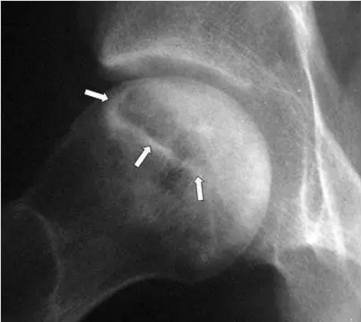

患者的臀部的蛙式位图片,新月征显示缺血坏死志,表明软骨下骨折。 一旦出现这种迹象,治疗性干预就不太可能阻止疾病的进展。新月征是指股骨头负重区软骨下骨板内1~2mm厚的透光区,是由于骨坏死后,骨质被吸收,出现微骨折所致,通常在正位片上不易见到,在蛙式位片上易显示,容易被忽视。

在死骨和活骨之间的界面处的小梁骨,由于机械损伤可能加剧无血管坏死(AVN)。在软骨下区域,这种微裂缝不愈合,因为它们发生在死骨区域内。 微裂缝的进展导致弥漫性软骨下骨折,在放射学上看作新月形征(见下面第一图)。在软骨下骨折和进行性加重之后,关节软骨发生塌陷(参见下面的第二至第五张图)。继续骨折、坏死和进一步加重,可进展为退行性关节疾病(DJD)和关节溶解(参见下面的第二张图片和最后2张图片)。

该患者的缺血坏死显示新月标志,表明软骨下骨折。 一旦出现这种迹象,治疗性干预就不太可能阻止疾病的进展。